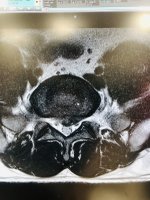

"Trọng Hoàng phát hiện mắc chứng thoát vị đĩa đệm trong đợt tập trung đội tuyển Việt Nam hồi tháng 9/2021 và phải nghỉ thi đấu tới nay. Lần gần nhất anh ra sân thi đấu trong trận tuyển Việt Nam thua Australia 0-1 ở vòng loại thứ ba World Cup 2022 hôm 3/9/2021. Hơn một năm qua, tiền vệ xứ Nghệ theo nhiều phương pháp điều trị nhưng thời gian đầu không hiệu quả. Anh sau đó quyết định phẫu thuật và tập phục hồi tại một trung tâm hồi phục chấn thương thể thao tại TP HCM do bác sĩ của đội tuyển quốc gia Trần Huy Thọ trực tiếp hướng dẫn"Mày sai rồi, Trọng Hoàng điều trị bảo tồn, nó sang Sing bên đó bảo mổ nó đéo mổ, về việt nam điều trị bảo tồn 3 thâng ok luôn.

Thông tin chính thống, mày tìm báo nào cũng ra, ko lại bảo tao bốc phét